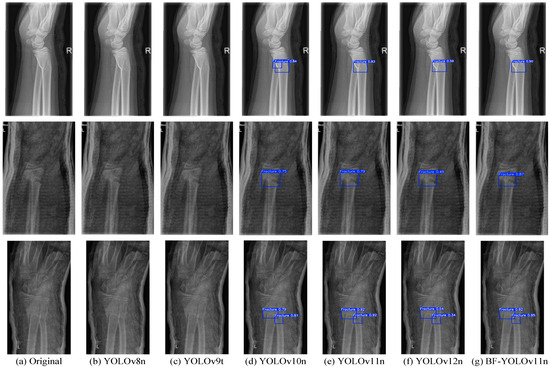

| Detection Models | p/% | R/% | F1 | mAP50/% | Parameters/106 | GFLOPs/109 | Inference/ms |

|---|---|---|---|---|---|---|---|

| SSD | 79.68 | 26.35 | 39.60 | 59.81 | 26.28 | 62.7 | 28.40 |

| YOLOv8n | 60.75 | 91.37 | 72.98 | 91.55 | 3.01 | 8.1 | 3.5 |

| YOLOv9t | 52.66 | 92.15 | 67.02 | 91.89 | 1.97 | 7.6 | 3.3 |

| YOLOv10n | 90.33 | 84.09 | 87.10 | 91.05 | 2.71 | 8.2 | 2.4 |

| YOLOv11n | 89.23 | 85.37 | 87.26 | 91.64 | 2.58 | 6.3 | 1.8 |

| YOLOv11n + ResNet_GAM | 93.47 | 85.90 | 89.53 | 92.53 | 5.39 | 15.2 | 4.3 |

| YOLOv12n | 74.95 | 90.02 | 81.80 | 91.42 | 2.56 | 6.3 | 2.1 |

| BF-YOLOv11n | 93.56 | 86.29 | 89.78 | 92.88 | 2.70 | 6.4 | 2.2 |